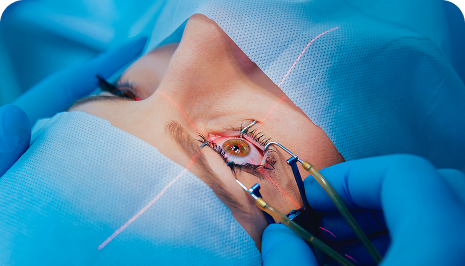

Cataract Surgery

What do you understand by Cataract? A cataract is an eye condition characterized by the clouding of the natural lens in the eye, leading to

LASIK Surgery

What is LASIK Surgery? LASIK (Laser-Assisted In Situ Keratomileusis) or laser eye treatment is a popular laser eye surgery technique that is